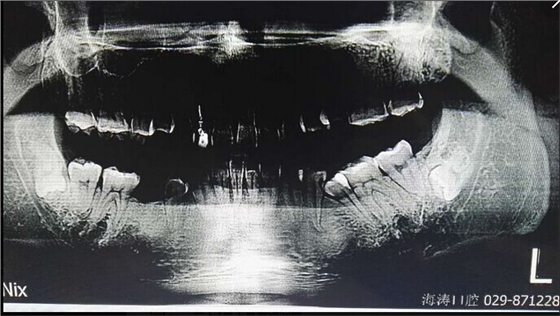

討論一:可以上托超拉拉,再拔

討論二:靜觀其變、個(gè)人覺得無任何癥狀可先予觀察不做處理!

討論三:阻生智齒沒有暴露在口腔是可以不予理睬,可以長期埋伏與人共存的。除非有特殊要求或變化。

提問:對7號(hào)牙沒有影響的埋伏智齒,是不是可以不拔?

答:一般情況下,完全骨埋伏阻生牙患者如無不適癥狀不會(huì)要求撥牙的,很多時(shí)候是口腔內(nèi)其它問題拍片時(shí)發(fā)現(xiàn),但醫(yī)生發(fā)現(xiàn)這種情況要告知患者將來可能會(huì)發(fā)生什么問題,例如頜骨囊腫,7號(hào)牙松動(dòng)等等,畢竟這個(gè)8號(hào)牙是潛在的病灶牙,究竟撥與不撥得讓患者作主,我們得盡到告知義務(wù)。往往最后決定撥這類牙的患者都是有各種不適癥狀的。

至于對7號(hào)牙暫時(shí)沒有影響的埋伏牙,不等于以后永遠(yuǎn)不影響。